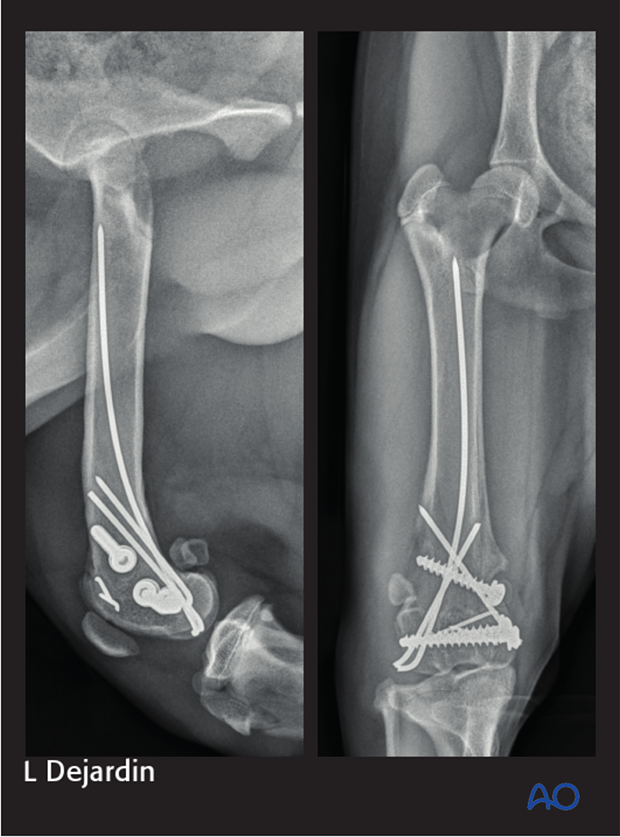

Postoperative radiographs should be taken to assess the repair.

Radiographic assessment is performed every 4-8 weeks until bone healing is confirmed.

Implants may be removed if there is irritation or infection present, however if they are not causing problems for the patient, there is no need for implant removal.